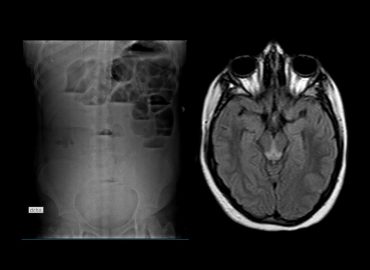

Pte de sexo femenino, 60 años. MC Dolor epigástrico

Distensión abdominal